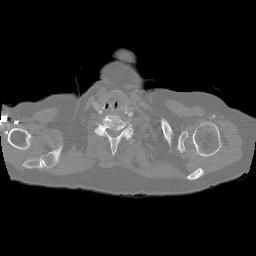

4.5.2 Quantum Noise

To test the proposed method’s performance under the low-dose condition, we repeat the aforementioned reconstruction experiments by using the sinogram data polluted with Poisson-distributed noise. The average number of X-ray photons received by the th detector can be expressed as:

where is the blank measurement (). It is worth mentioning that the sinogram measurements employed in this study are derived from simulations, as opposed to being sourced from an actual instrument. Thus, here is a parameter for relative measurement. Throughout the experiments, is assigned values ranging from to , which correspond to sinogram SNR (dB) values of . It is worth mentioning that analogous experiments were conducted under both few-view and limited-angle scenarios, with the proposed method demonstrating a marked superiority over other methods across all conditions. This enhancement, however, is primarily attributed to the exceptional performance of the proposed method under sparse-measurement circumstances, rather than an increased resistance to noise. To facilitate an equitable comparison, the results displayed in Fig.11 are solely derived from the full-view scenario, which encompasses an angular range of with one view per degree.

(a) ASD-POCS (19.92dB)

(b) RBP-DIP (23.82dB)

(c) DIP (21.88dB)

(d) MED50 (15.61dB)

5 Discussion

In practical applications, the imaged object might exhibit inconsistencies with the training dataset due to various non-ideal factors. The rotation operation in Section 4.5 serves as a simplified simulation of such discrepancies, which may arise from differing poses of patients. The impact on reconstruction accuracy is shown in Fig.9. The comparison between Fig.5b and Fig.9 reveals that the pre-trained MED50 method is predominantly affected by a considerable decline in SNR. The reconstruction results are also presented in Fig.10. In contrast to the first row of Fig.7, the MED50 reconstruction result lacks a completely black background and exhibits horizontal artifacts in the non-empty region. This observation suggests that MED50 cannot effectively handle the perturbations in the inference data.

Additionally, experiments were conducted under low-dose conditions, as demonstrated in Fig.11. MED50 was found to be the most vulnerable to sinogram noise, while RED-CNN exhibited relative insensitivity to perturbations due to its patch-based learning approach.

The proposed RBP-DIP framework does not necessitate any training images and attains the highest reconstruction accuracy in both experiments. Moreover, additional constraints or regularizations can be directly incorporated into the objective function or indirectly integrated into the RBP connection, enabling enhanced handling of various factors without retraining.